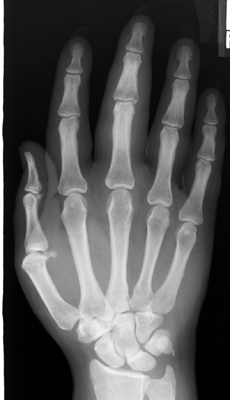

X-ray of the hand with diffuse fusiform soft-tissue swelling of the entire 3rd digit. This sign refers to fusiform soft-tissue swelling involving an entire, single digit within the hand. The appearance of a sausage digit (cocktail sausage) is classically associated with the single-ray pattern of involvement seen in some patients with psoriatic arthritis, and may be the initial manifestation of the disease.

PA hand - Click on the image for a larger version